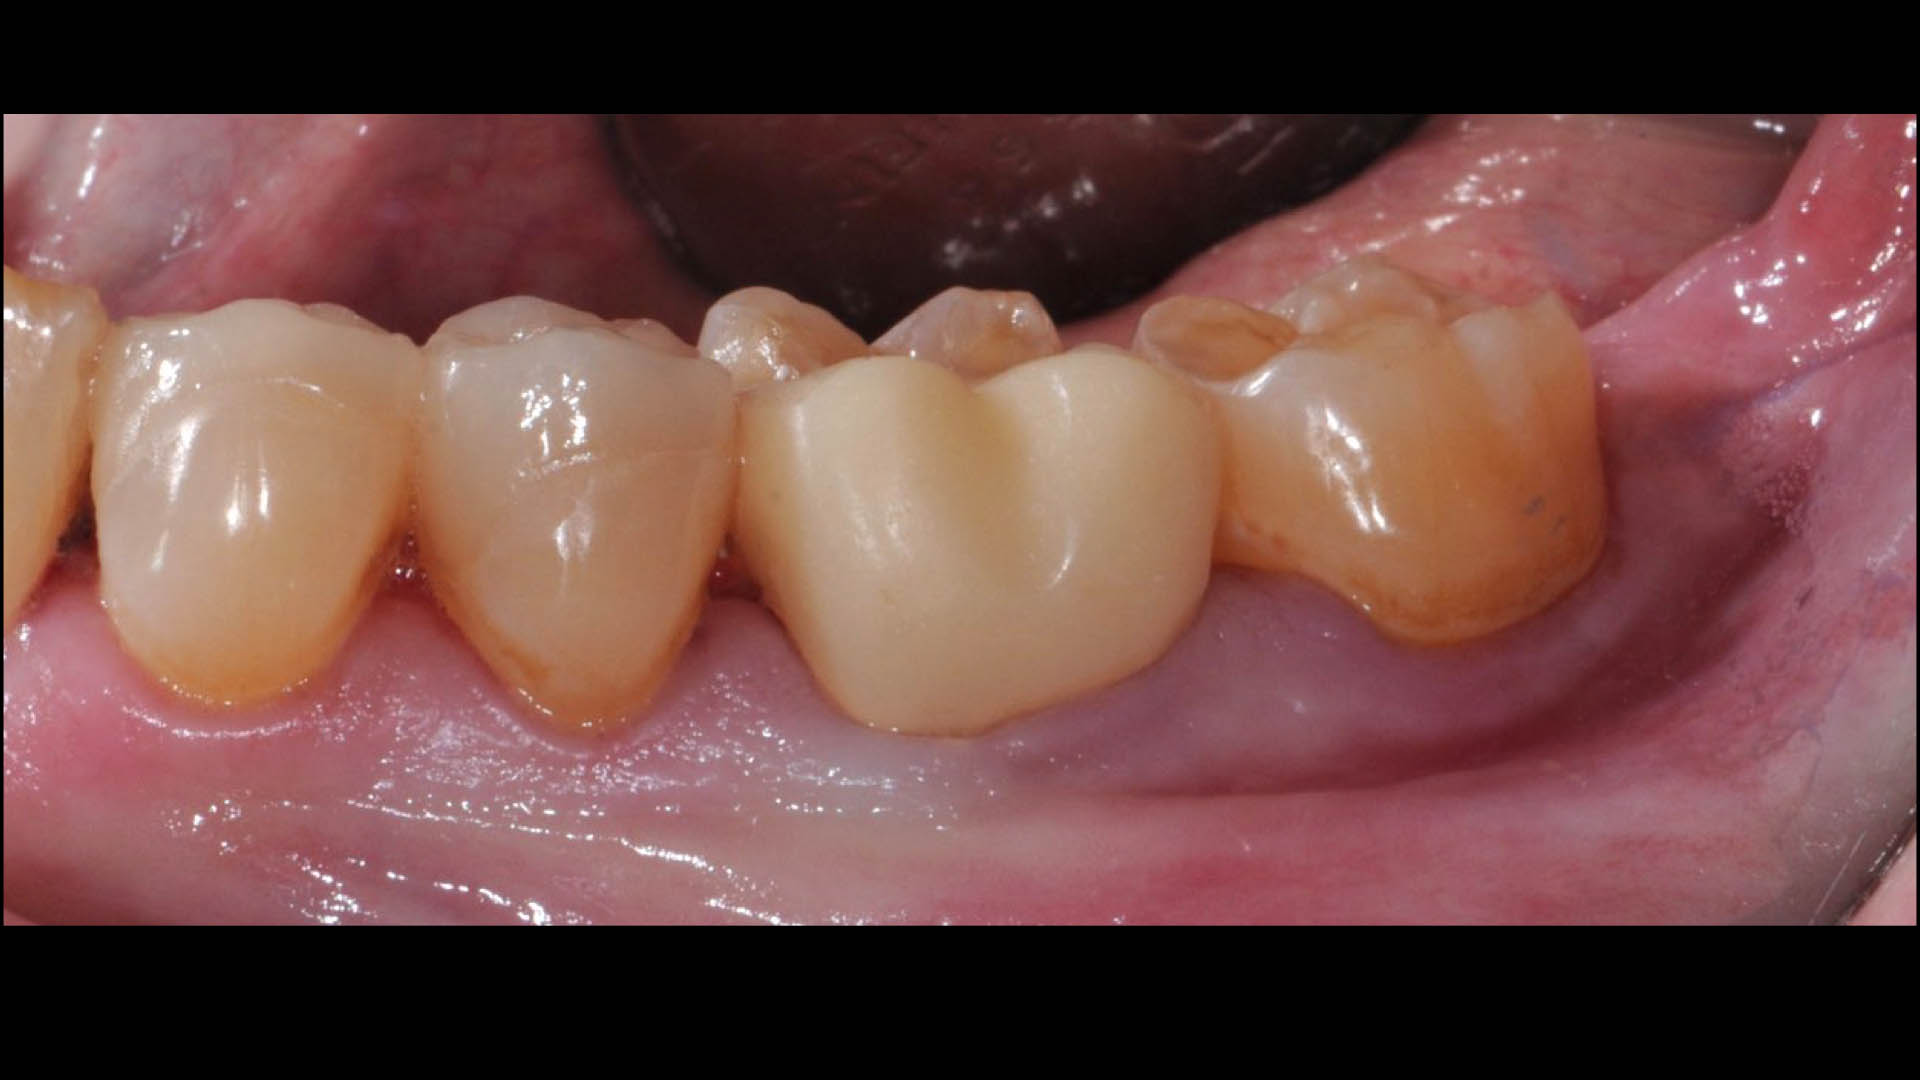

Take a glimpse into the magic of Coral Gables Dentistry through our before and after pictures. See firsthand the incredible smile makeover transformations that have brought confidence and joy to our patients.